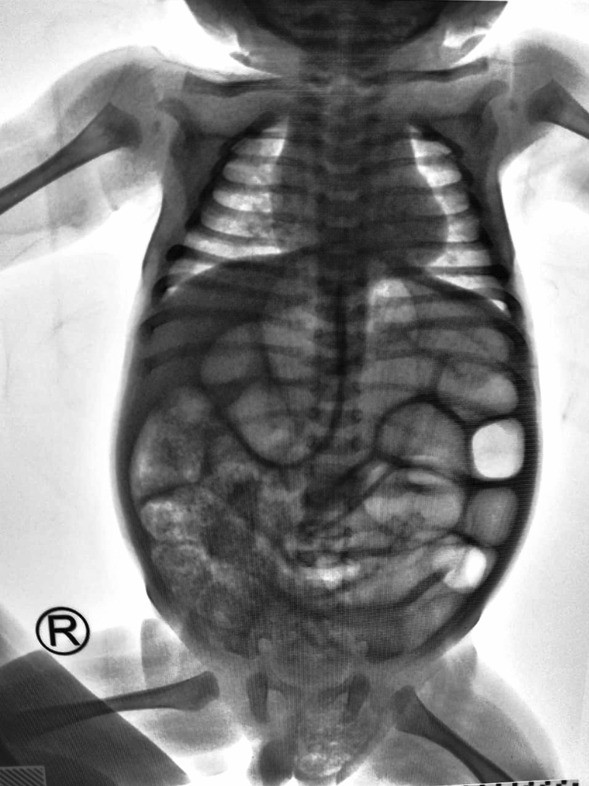

Fig. 2From: Left-side incarcerated Amyand’s hernia with appendix and caecum provoke by early banana diet: a case reportX-ray’s examination. This is the X-ray examination in the Emergency Department. We can see obstructed bowel and caecum in the left inguinal herniaBack to article page